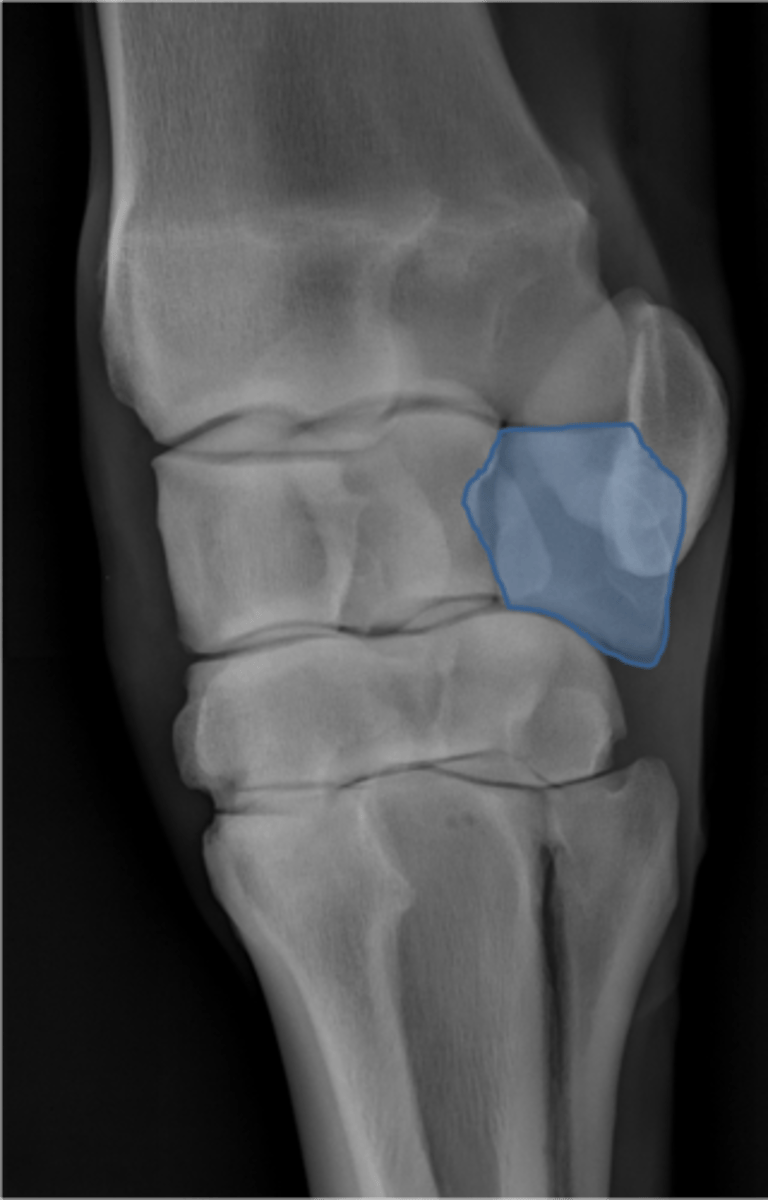

Carpus, lateral

ID joint and view

Antebrachiocarpal joint

Middle carpal joint

Carpometacarpal joint

Radial carpal bone

Intermediate carpal bone

Ulnar carpal bone

Third carpal bone

Second carpal bone

Fourth carpal bone

Accessory carpal bone

Second metacarpal (medial splint)

Fourth metacarpal (lateral splint)

Cannon bone